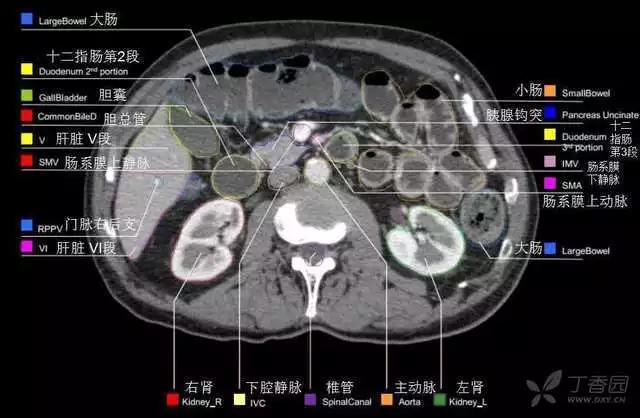

腹部肝脏高清CT断层的图谱

全腹部高清CT图谱,淋巴结彩色图谱,血管解剖图谱大汇总!

肝段,肝内管道的分布规律